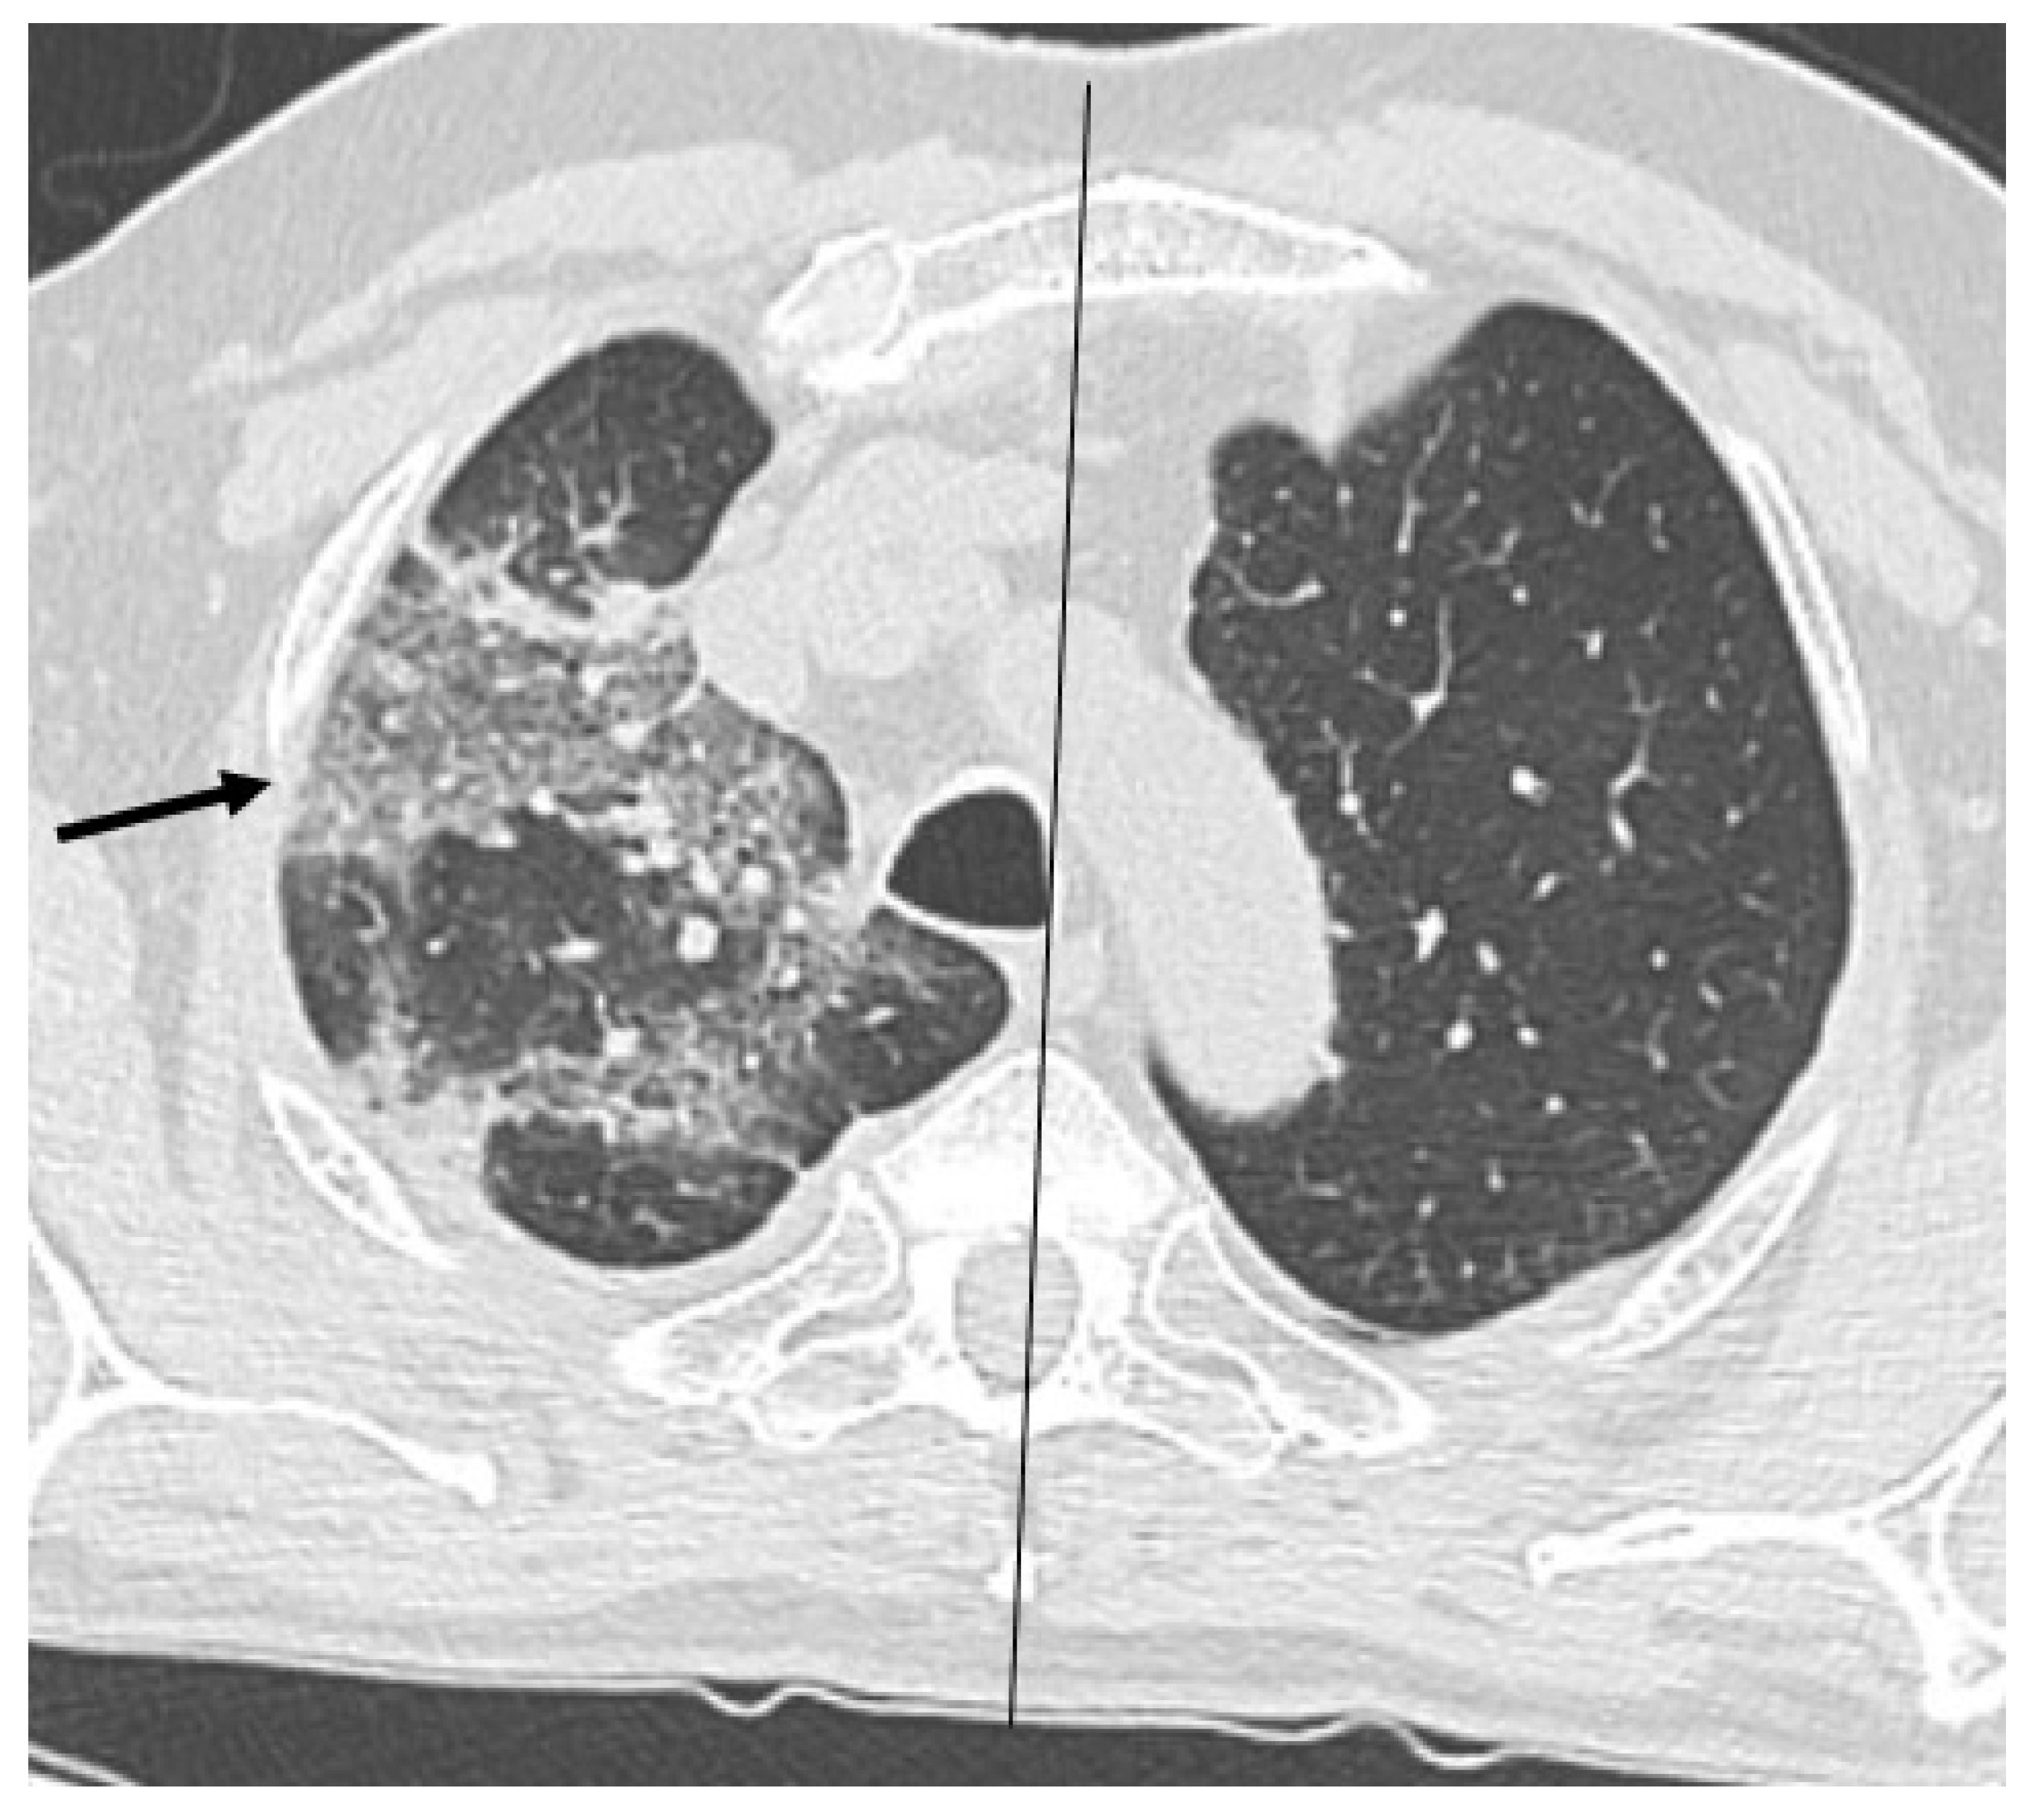

HRCT of the chest showed diffuse bilateral ground glass opacities (GGO) in all patients (Figure 1). Reticulation (Figure 2), traction bronchiectasis/bronchiolectasis (Figure 3), crazy paving and distortion (Figure 4) were observed in 29 patients (64%) at baseline. The total severity score was significantly higher at baseline in patients who eventually developed severe versus non-severe ARDS and pneumomediastinum/pneumothorax (16 versus 14; 95% CI 0.42 to 3.88; p = 0.01), as reported in Table 1. No other significant difference was observed at baseline.

Figure 3.

Bronchiolectasis (arrows) in the right lung.

It has been reported that pneumomediastinum in SARS-CoV2 ARDS may be related to lung frailty more than barotrauma [18]. In our population lung involvement assessed by HRCT revealed an extensive GGO. The median total severity score was 16/20, so that in each lobe coexist pathological and normal groups of alveoli. This condition implies an uneven distribution of pressure during ventilation. In addition, frequently observed abnormalities include reticulation and bronchiolectasis which suggest a parenchymal distortion and possibly a reduction of lung compliance. Crazy paving is an interlobular and intralobular septal thickening, also common in ARDS. It is sometimes a cause of parenchymal distortion eventually leading to loss of lung volume and impaired compliance. We suggest that interstitial pneumonia can lead to architectural distortion and reduced compliance. This reflects on recruitability, in fact, in this condition lungs can tolerate a small variation or pressure, or driving pressure during non-invasive ventilation.